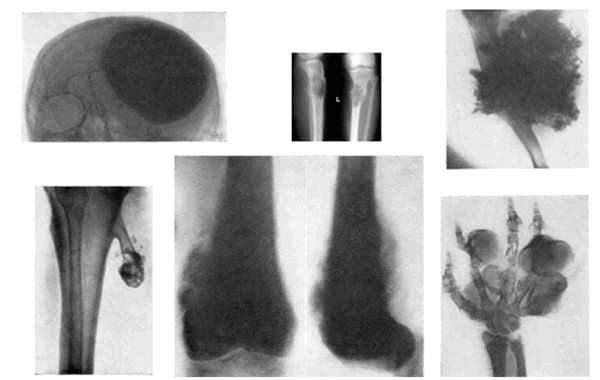

Как правило, опухоль поражает длинные кости конечностей (около 80 % всех случаев). Чаще всего первичный очаг локализуется в бедренной кости (около 45 % случаев), большеберцовой кости (18-20 %) и плечевой кости (10 %). Остальные случаи приходятся на редкие локализации: кости черепа (8 %), кости таза (8 %) (рис. 1).

Рис.1: Варианты локализации остеосаркомы

Характерные рентгенологические признаки остеогенной саркомы (рис. 2):

- деструкция и склероз костной ткани в зоне поражения;

- периостальный козырек Кодмена, представляющий из себя отслоенную опухолью надкостницу;

- игольчатый периостит с множественными костными иглами-спикулами;

- очаги патологического костеобразования в мягких тканях (поля оссификации) в области образования;

- патологический перелом пораженной конечности.

Рис. 2. Рентгенологические признаки остеогенной саркомы